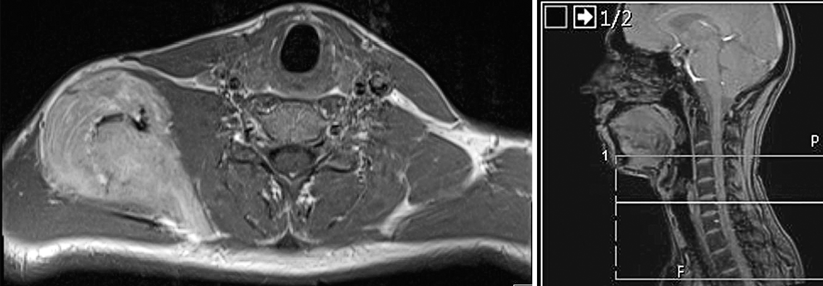

Obwohl etwa ein Viertel der Erkrankten mit HNSCC einer älteren Gruppe zuzuordnen sind und für diese bisher wenig Studiendaten vorliegen, gibt es hier dennoch Behandlungsfortschritte. © Satjawat – stock.adobe.com